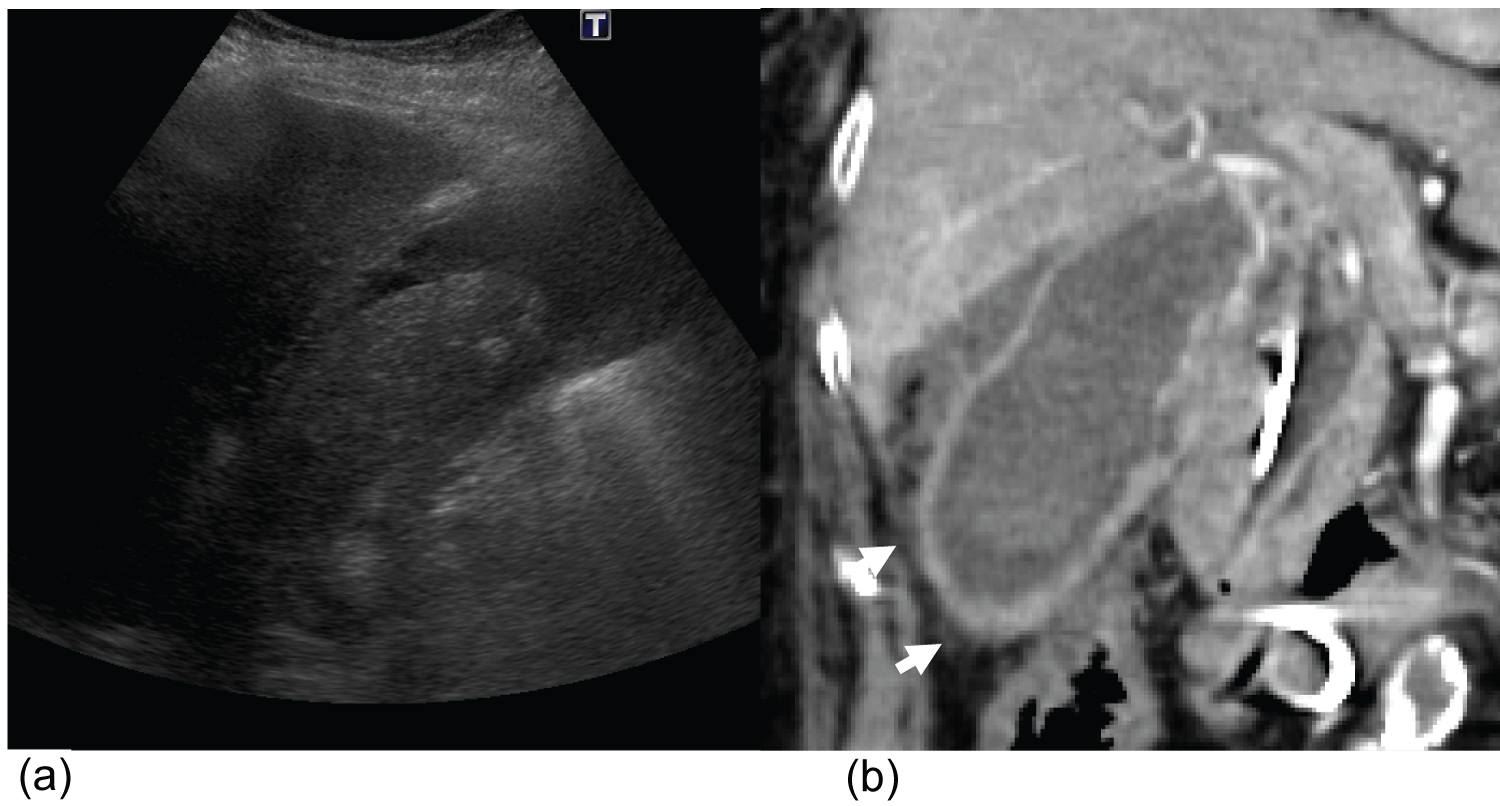

Figure 1: A 60-year-old man with acute calculous cholecystitis (histologically proven).

Longitudinal (a) and transverse (b) ultrasound imaging of the gallbladder. A single 3-cm mobile gallstone can be seen. No appreciable gallbladder wall thickening or probe tenderness was noted. Portal venous phase CT abdomen and pelvis (performed approximately 48-h later) demonstrated pericholecystic fat stranding (arrows) and gallbladder wall hyperenhancement. View Figure 1